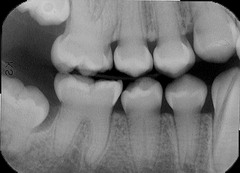

dentinogenesis imperfecta on radiograph

Front

Back